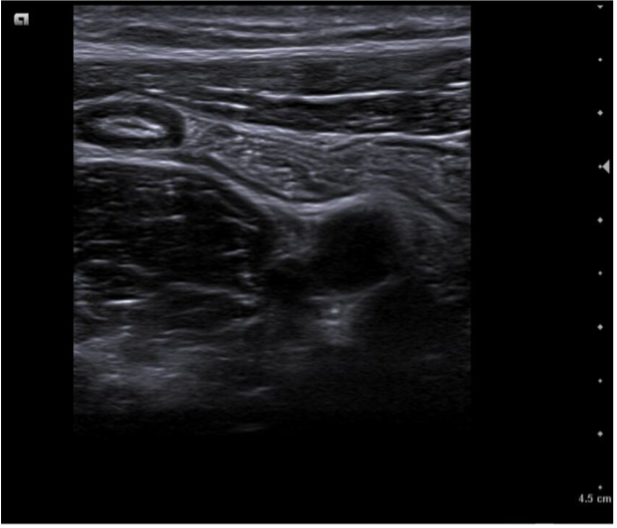

Caso 1. Asa intestinal en FID con poca movilidad (vista con sonda lineal) posible apendicitis.

Caso 2. Asa intestinal fija con edema de pared por posible apendicitis o ileitis. Corte transversal con signo del donut.